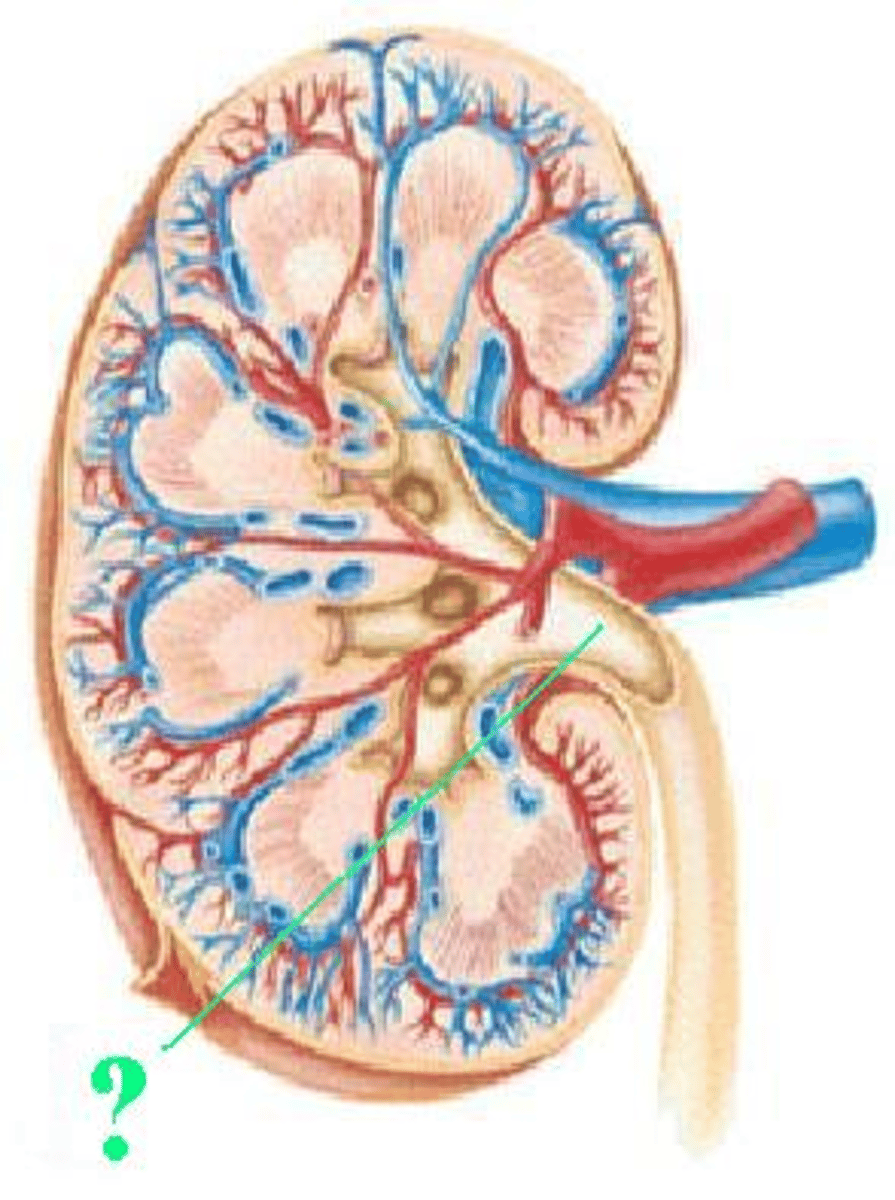

cortex

Identify the indicated region of the kidney.

renal column

Identify the indicated structure.

arcuate vein

Identify the indicated vessel.

interlobar vein

segmental artery

medullary pyramid